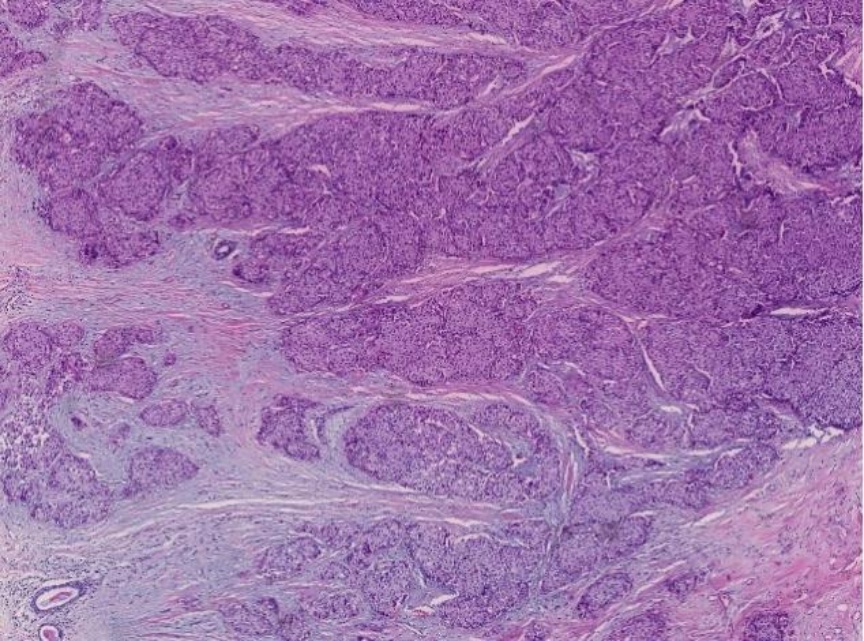

镜下观察原位型SPC可见肿瘤细胞形成富于细胞的实性结节,呈膨胀性生长模式(图1(A)),结节内可见纤细的纤维血管轴心结构(图1(B)),肿瘤细胞形态相对一致,异型性呈轻至中度,核分裂象罕见。SPC伴浸润,浸润区表现为轮廓不规则、地图样或锯齿状的肿瘤细胞巢侵入周围间质并伴促纤维结缔组织反应(图2);1例(病例7)则在SPC背景的基础上,明确伴有黏液癌成分(图3),黏液湖中漂浮着大小不一的肿瘤细胞簇。

Figure 2. Breast carcinoma, solid papular type, with invasion. The invasive component is characterized by irregularly contoured, geographic or jagged tumor cell nests infiltrating into the surrounding stroma, accompanied by a desmoplastic stromal reaction (HE ×40)

2. 乳腺实性乳头状癌伴浸润,浸润区表现为轮廓不规则、地图样或锯齿状的肿瘤细胞巢侵入周围间质并伴促纤维结缔组织反应(HE ×40)